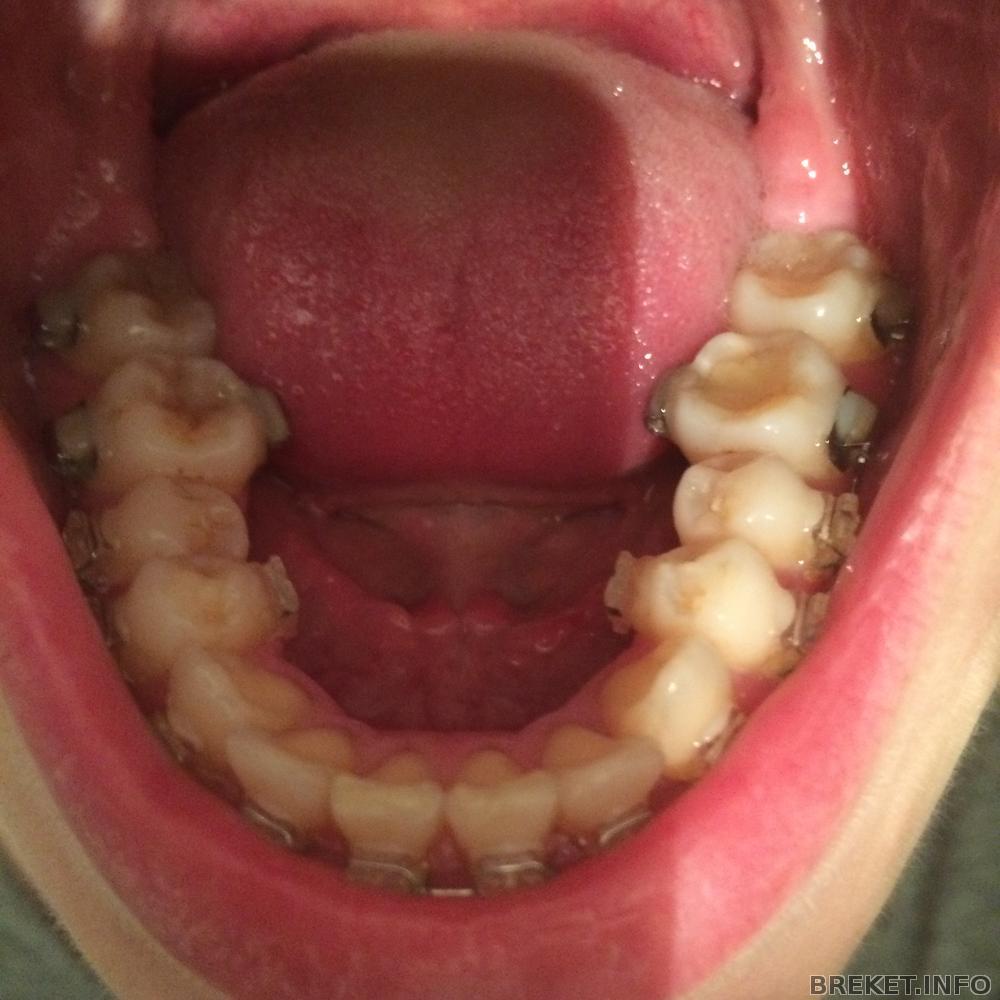

Ксеничка, да, это штука для расширения челюсти, сфотаю попозже. если честно, ожидала, что будет прям больно сильно, готовилась к худшему, начитавшись отзывов. но было не так больно и сейчас меня этот аппарат не так сильно беспокоит, как брекеты, которые мне наклеили с внутренней стороны нижней челюсти, чтоб цеплять за них тяги. вот эти девайсы мне раздирают язык, не могу из-за них кушать, хотя уже прошло больше недели(((

Спасибо за пожелания и фото!) Какие ушастые зубки получаются с двумя брекетами))) Или это ручки у них

upd А, поняла, они как будто в наушниках пушистых на зиму